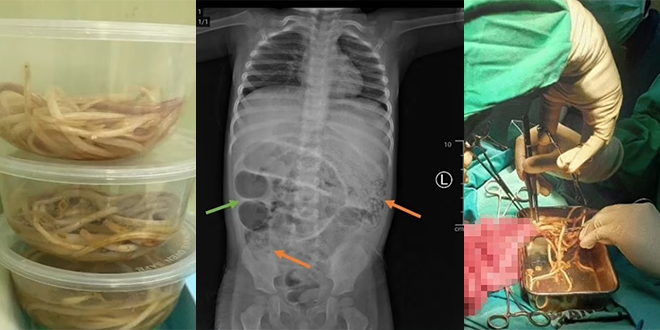

في البداية تم تشخيص الصبي بالإمساك، وفق “دايلي ميل”. ولكنه بدأ يتقيأ ديداناً في اليوم التالي، وأظهرت الأشعة السينية في معدته كتلاً رمادية، ما دفع الأطباء للاشتباه في وجود انسداد معوي حاد.

وعلى الفور، خضع الطفل لعملية جراحية عاجلة، تم خلالها فتح البطن، ليُفاجأ الفريق الطبي بوجود ديدان تسد ثلاث مناطق منفصلة من أمعائه الدقيقة.

وخلال العملية، قام الأطباء بشق جزء من الأمعاء الدقيقة على بُعد نحو 50 سم من التقاءها بالأمعاء الغليظة، ثم أخرجوا الديدان يدوياً قبل خياطة الأمعاء وإرسال العيّنات للفحص المخبري.